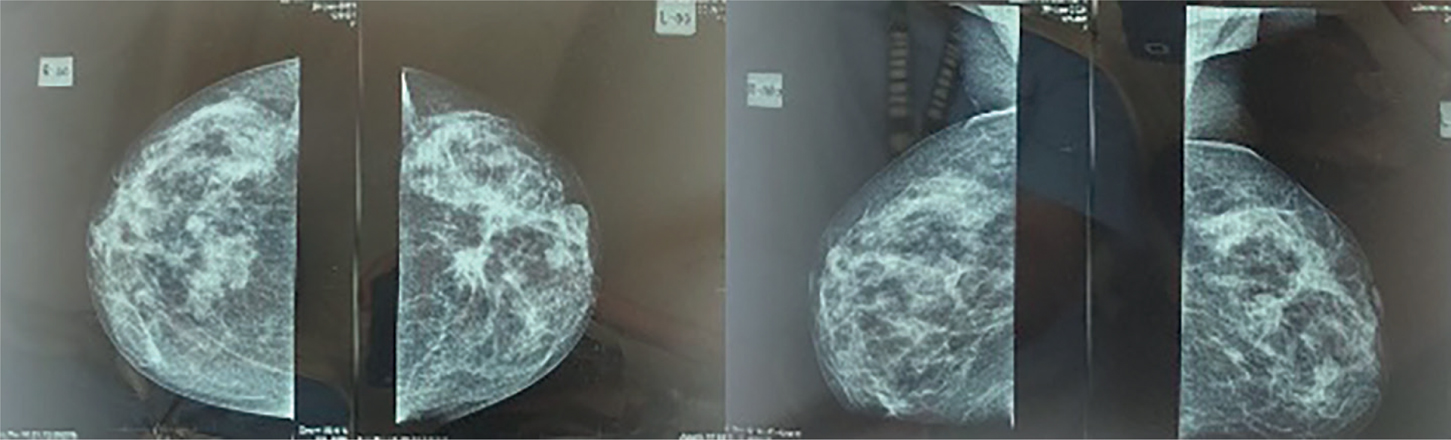

Post-operative MFBI or MRI is not routinely implemented to evaluate outcomes of surgical procedures due to strong enhancements of inflammatory tissues post-operatively in the acute phase. Consequently, immediate breast MRI is not recommended until 12 to 18 months after the procedures. The current guidelines do not recommend MFBI in treated breast cancer, and MRI is mostly indicated if recurrence of metastatic foci is suspected. However, breast MRI is eventually superior to detecting developing neo-density or other suspicious structures (7, 52, 53). In post-surgery settings, the result of MRI imaging is classified into enhancing mass, non-mass-like enhancement (NMLE), or suspected foci––with the characteristic of each focus fully described, for example, size, shape, margin (smooth, irregular, or even spiculated), and internal enhancement pattern (Figure 2). NMLE findings are elaborated according to their distributions along the breast tissue (focal, regional, segmental, scattered, or involving multiple regions), internal enhancement pattern, and symmetry. Foci that are too small to be optimally described (usually ≤5 mm in diameter) are defined as “indescribable” lesions (5355).

Fig 2

Figure 2. Malignant findings on breast MRI. Image provided by Division of Oncology, Department of Surgery, Faculty of Medicine, Universitas Sumatera Utara)